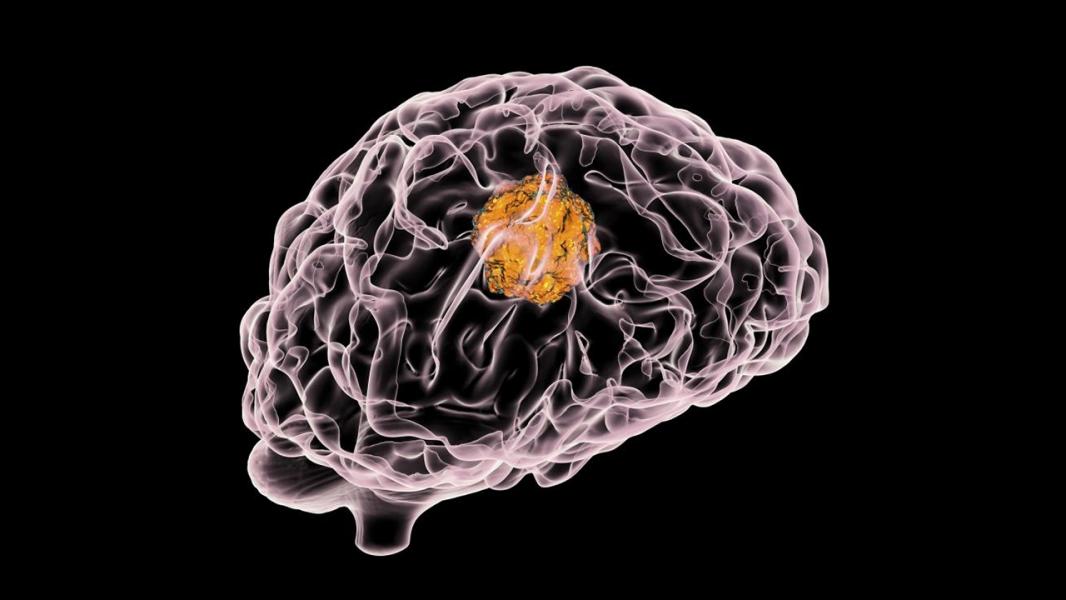

نانوربات مغناطیسی میتواند شانس درمان سرطان مغز را افزایش دهد

به گزارش خبرگزاری مهر به نقل از ستاد توسعه فناوری نانو، گلیوبلاستوما (GBM) شایع ترین و تهاجمیترین نوع سرطان مغز است. با وجود گزینههای مختلف درمانی که وجود دارد، از جمله عمل جراحی، رادیوتراپی و شیمی درمانی، زمان بقای متوسط برای بیماران فقط حدود ۱۵ ماه است.

شیمی درمانی استاندارد گلیوبلاستوما با استفاده از دارویی به نام تموزولومید (TMZ) انجام میشود که امید به زندگی فرد را تقریباً دو ماه در مقایسه با بیمارانی که به تنهایی رادیوتراپی دریافت میکنند افزایش میدهد. با این حال، سلولهای گلیوبلاستوما میتوانند با گذشت زمان مقاومت در برابر TMZ ایجاد کنند و اثربخشی آن را کاهش داده و احتمال عود تومور را افزایش دهند.

در یک مطالعه منتشر شده در Science Advances، زی هوانگ و همکارانش یک رویکرد جدید برای درمان گلیوبلاستوما با استفاده از کنترل مغناطیسی دقیق نانوذرات ارائه میدهند.